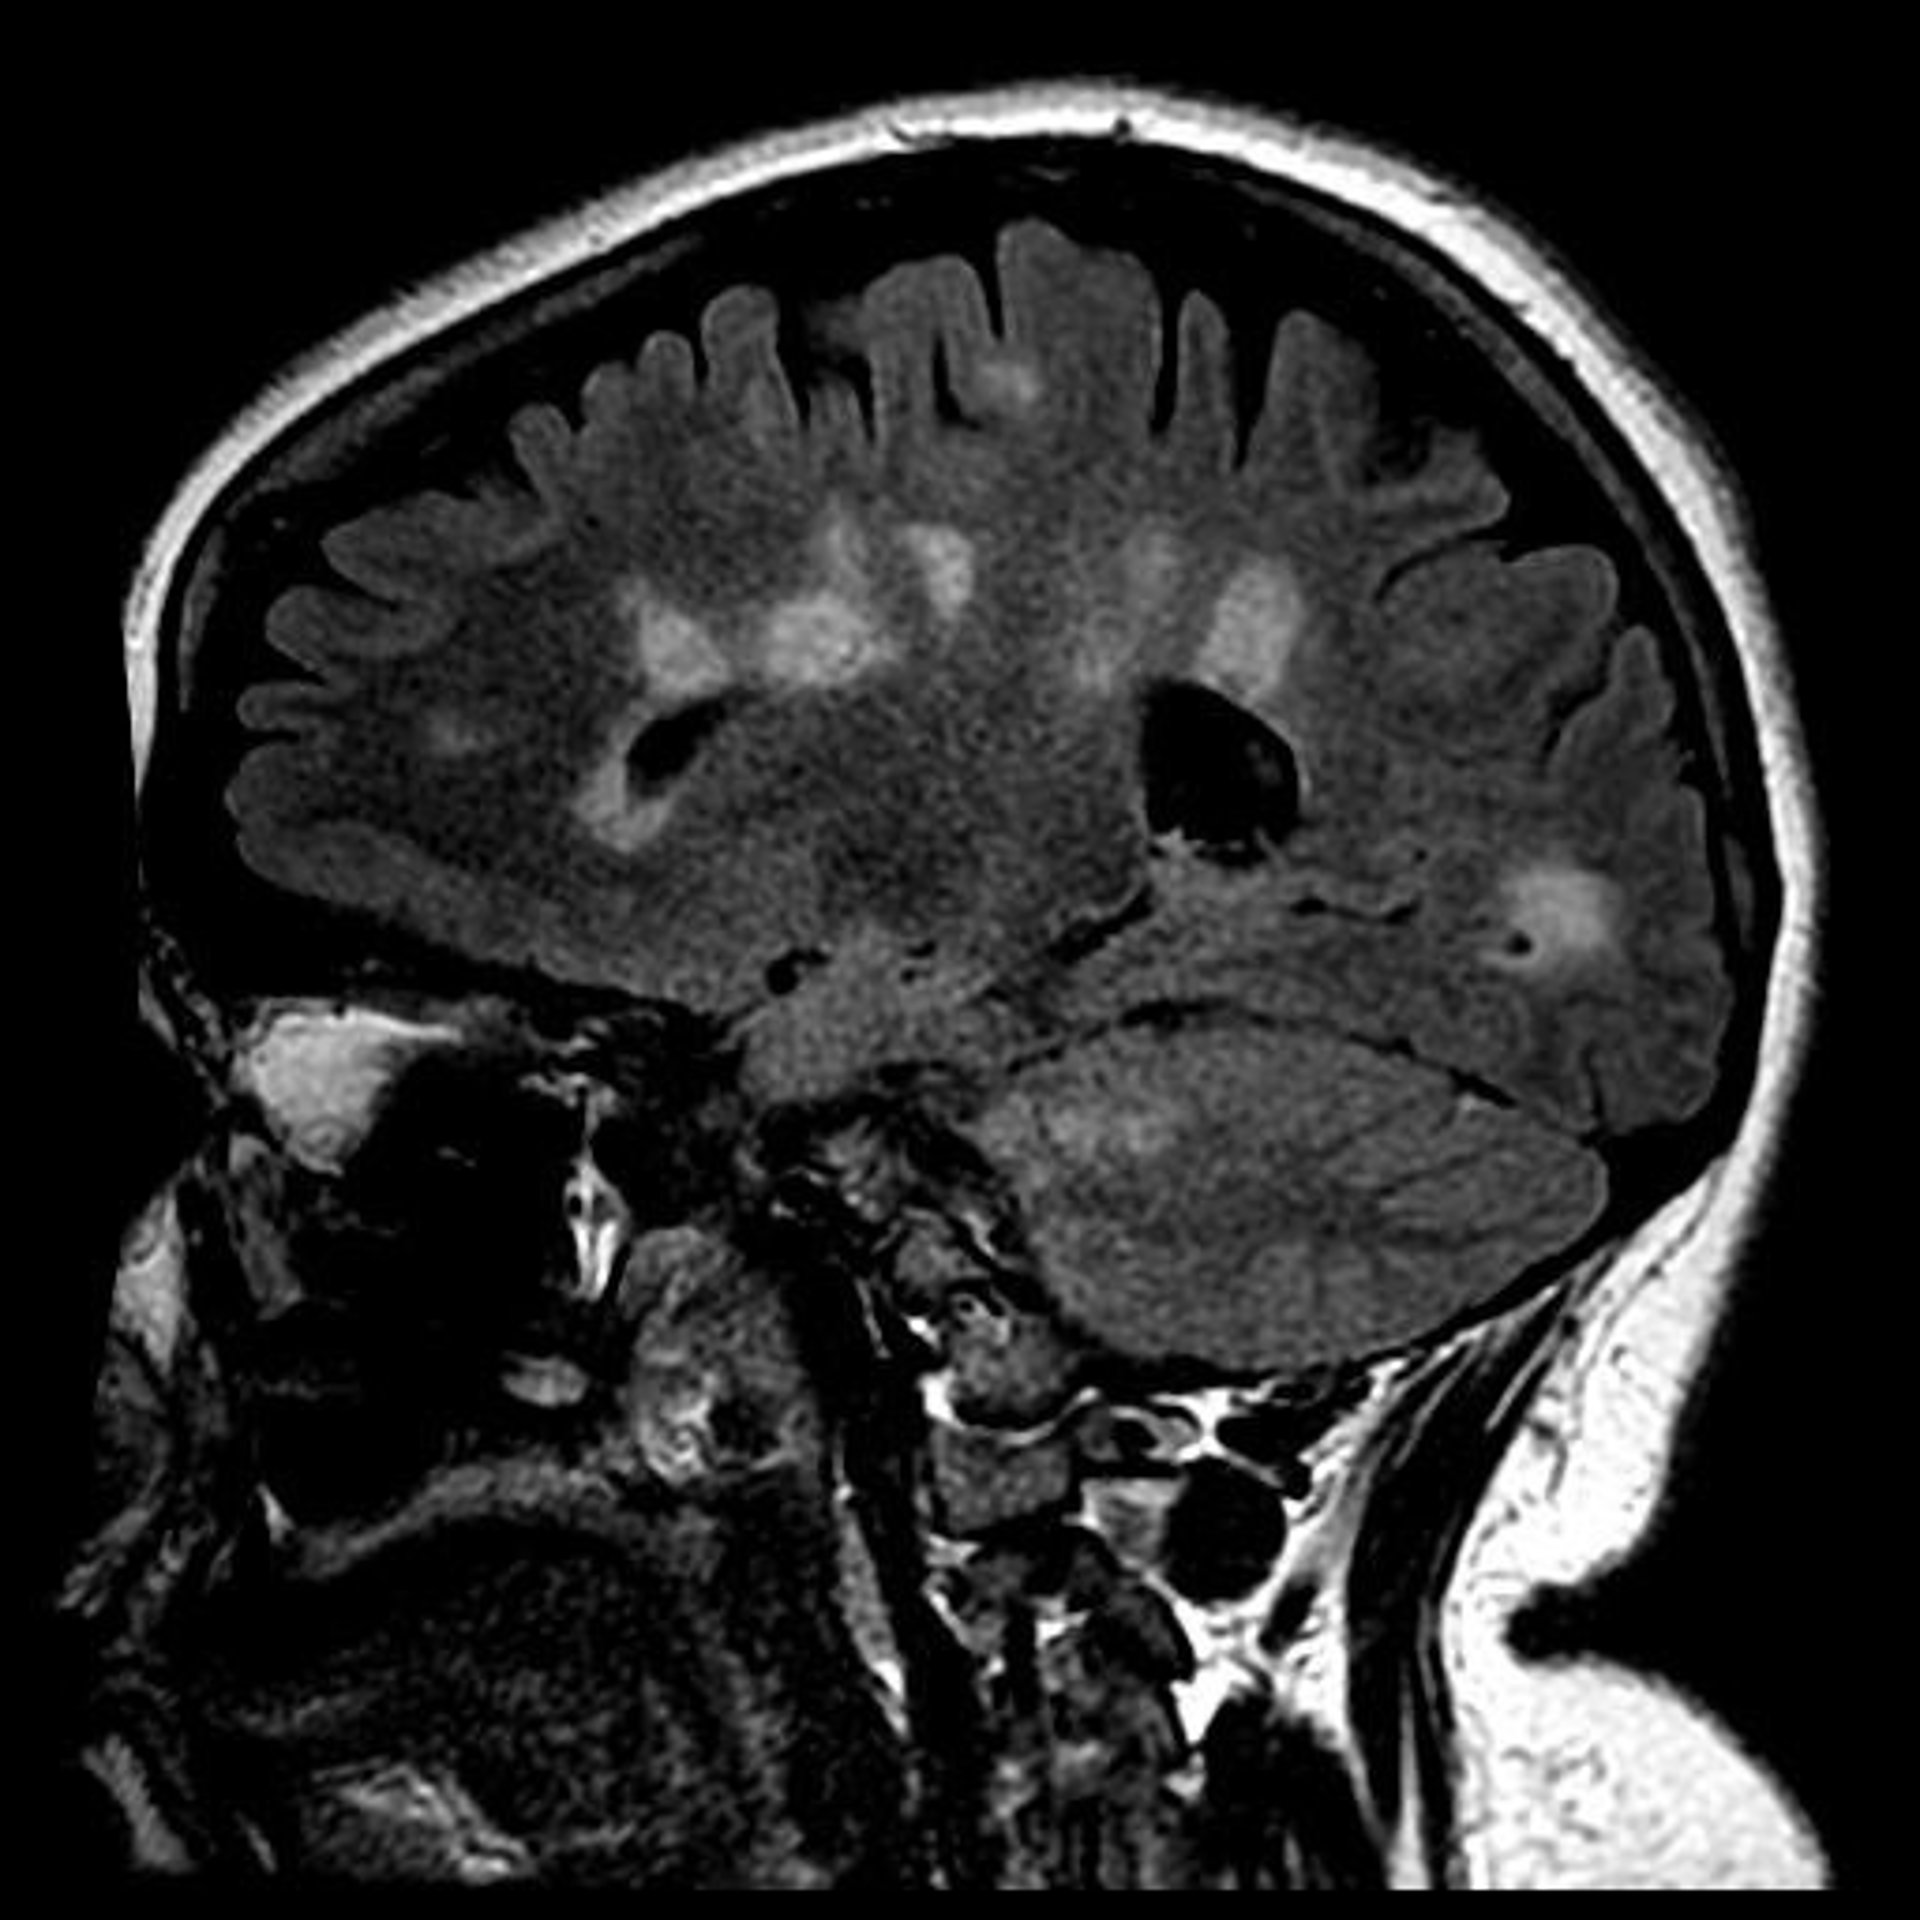

Cicatrización del cerebro en la esclerosis múltiple

Cicatrización del cerebro en la esclerosis múltiple - UNIVERSITY OF BRITISH COLUMBIA - Archivo